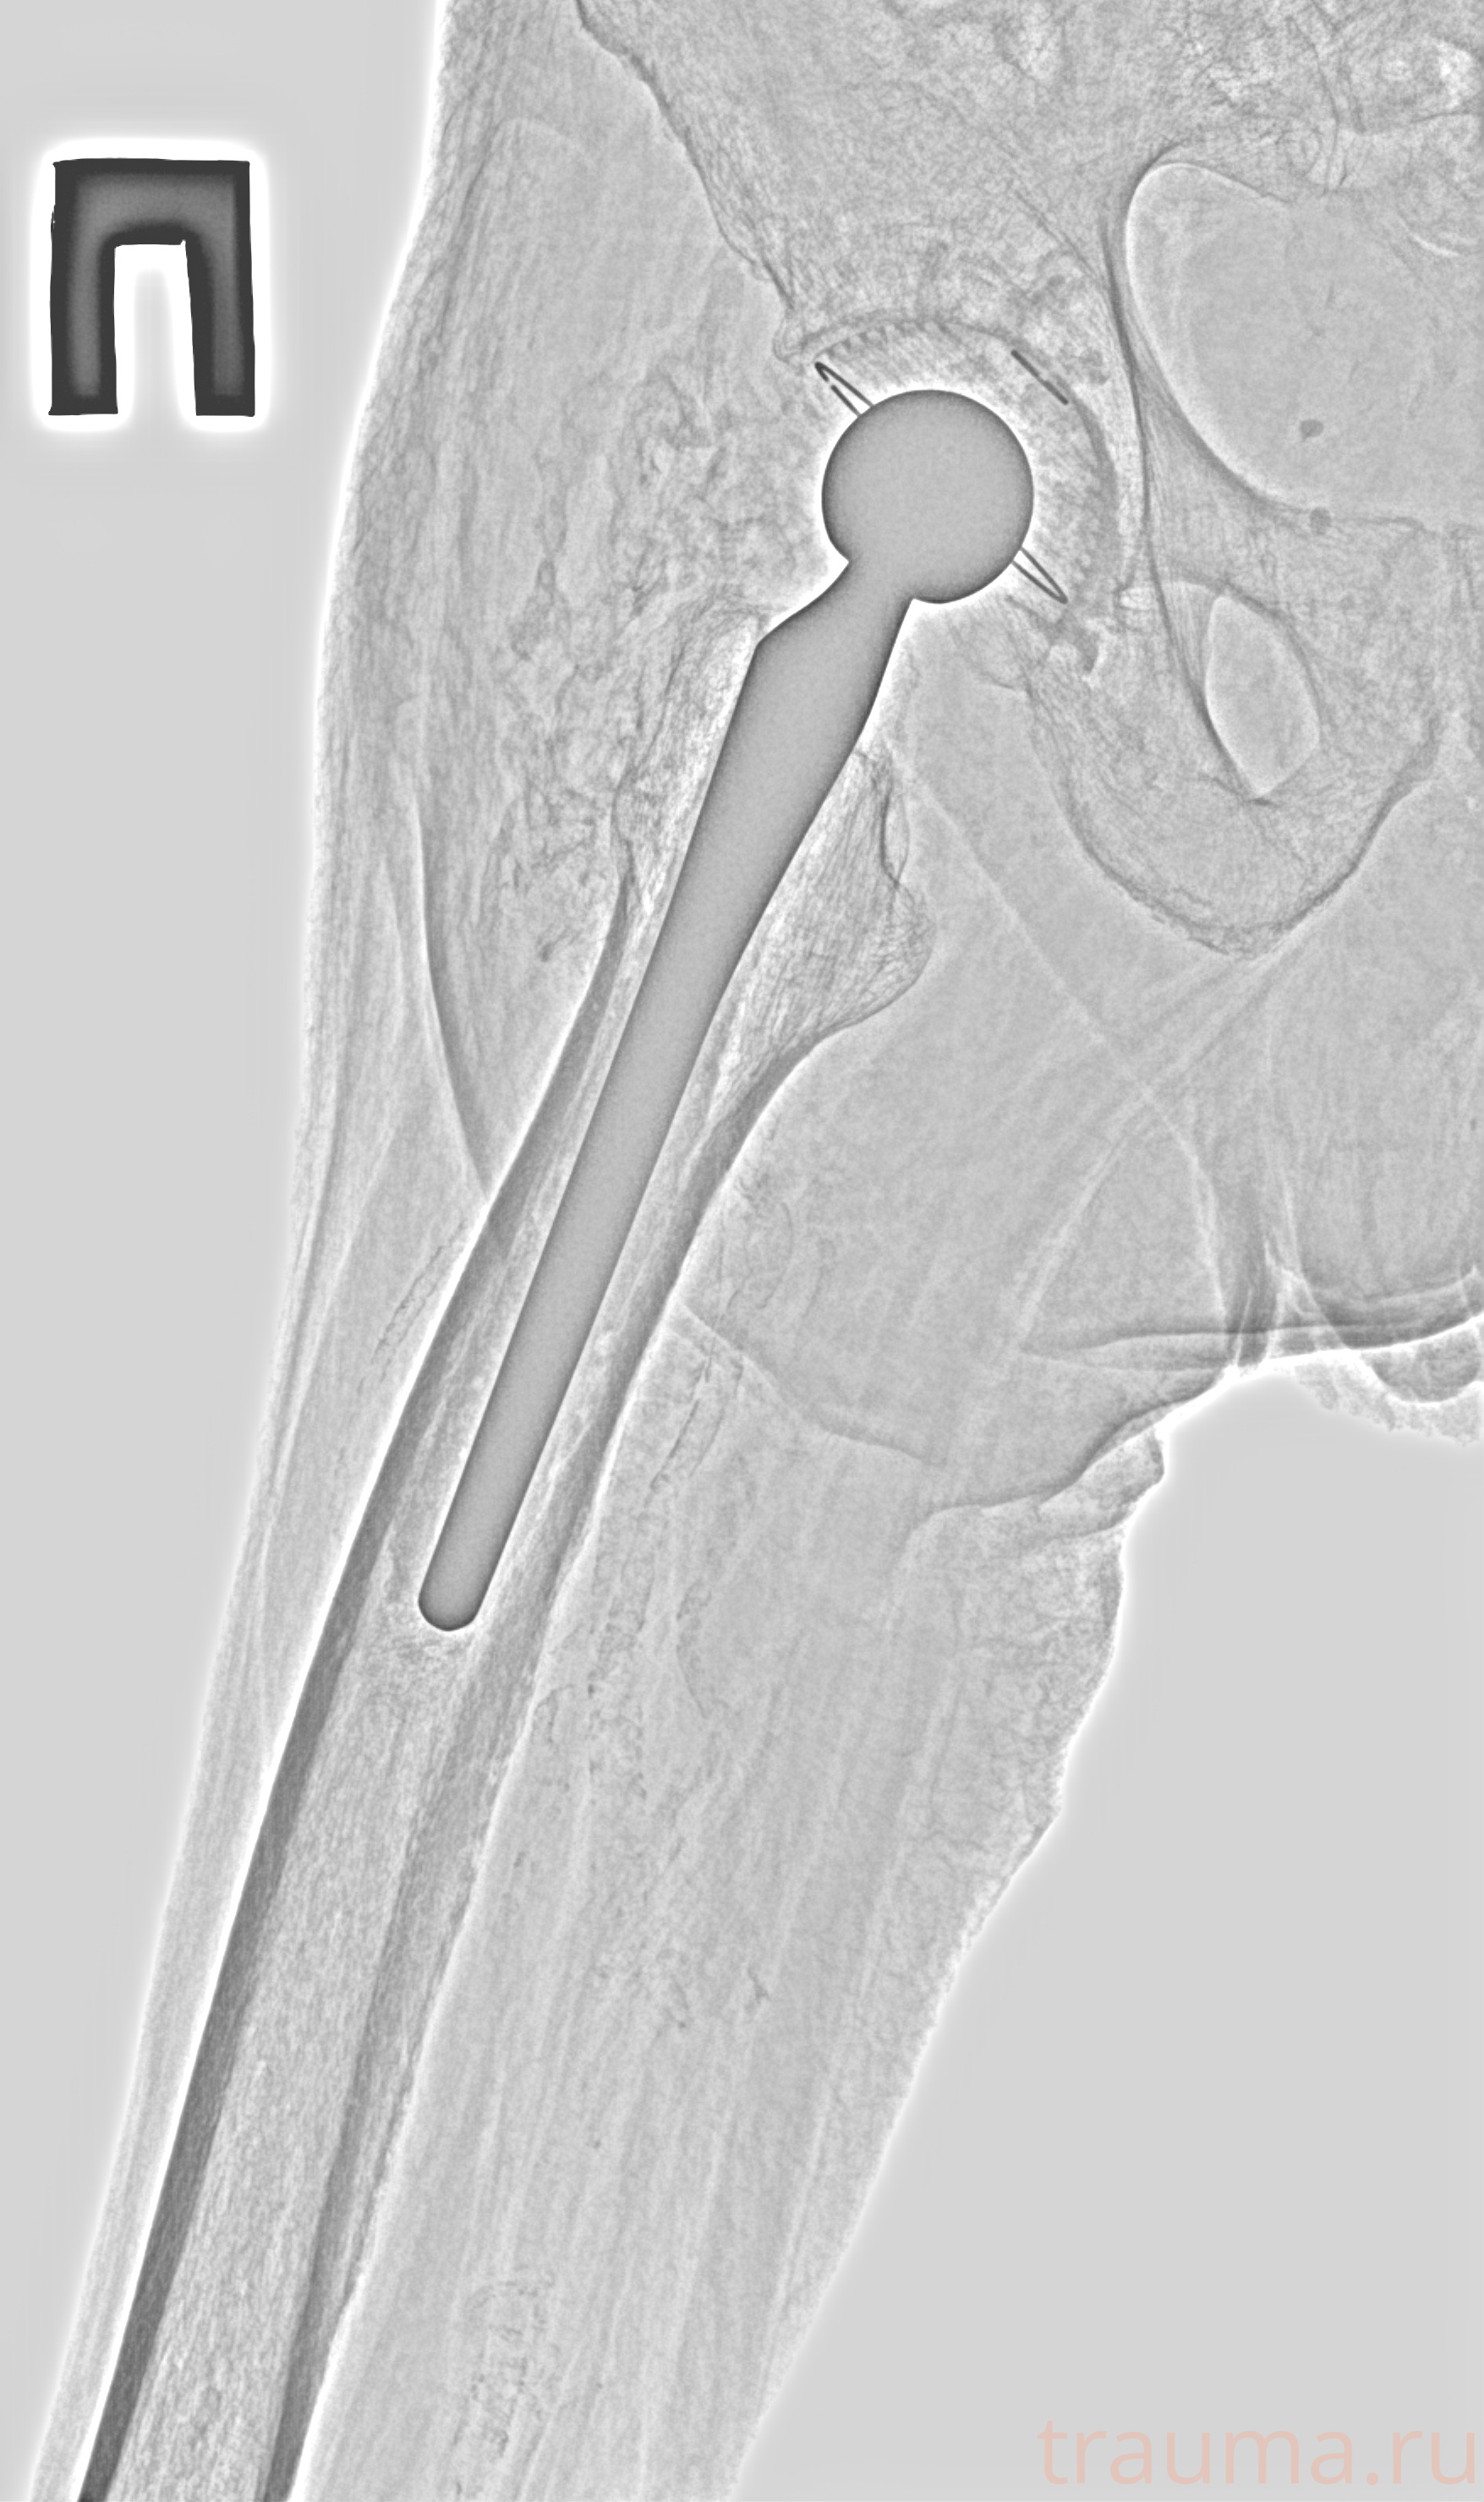

Рентген на дому: по вашему адресу приезжает врач-рентгенолог, травматолог-ортопед с мобильным рентгеновским аппаратом, проводит диагностику травмы или заболевания, делает необходимые рентгенограммы, дает рекомендации по дальнейшему лечению. Получить качественные снимки в домашних условиях возможно благодаря уникальной методике, разработанной МосРентген Центром для института  Склифосовского